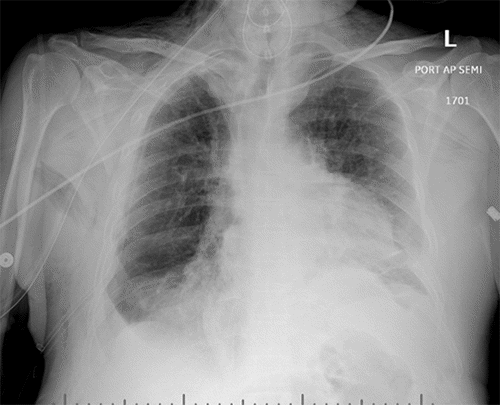

Figure 6. Chest X-ray on Postoperative Day 4 Demonstrating Right Hemidiaphragm Elevation. Published with Permission

Anteroposterior chest X-ray obtained on POD 4. Note marked elevation of the right hemidiaphragm compared to the immediate postoperative study (Figure 5), raising suspicion for diaphragmatic hernia recurrence or repair failure

An immediate postoperative chest X-ray (CXR) demonstrated an appropriate position of the right hemidiaphragm (Figure 5). Serial bladder pressure measurements were monitored for potential abdominal compartment syndrome due to the LOD; on postoperative day (POD) 0, bladder pressure was 16 mmHg. The patient required reintubation on POD 1 due to concerns for delirium tremens. On POD 4, he was successfully extubated and placed on 15 L/min of oxygen via nasal cannula. Concurrently, his bladder pressure acutely decreased to 9 mmHg. A follow-up CXR obtained after extubation revealed a significant elevation of the right hemidiaphragm (Figure 6). This finding, coupled with the change in bladder pressure and concern for herniated bowel visible on CXR, prompted an urgent CT scan of the chest. The CT confirmed recurrence of a large right diaphragmatic hernia containing the liver, small bowel, and colon.